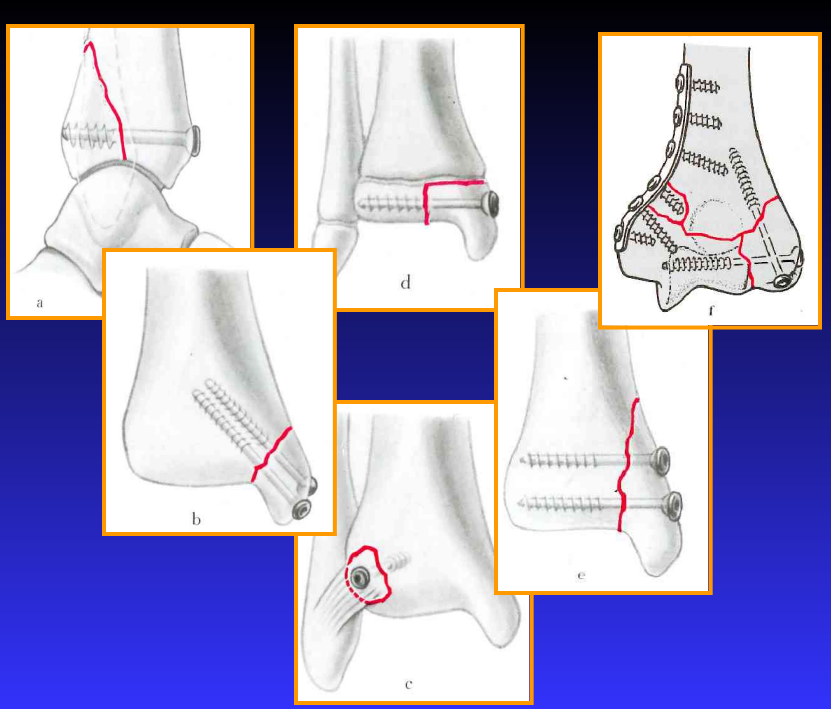

拉力螺钉的适应症

• 关节内骨折

• 干骺端骨折

• 中和钢板中的应用

拉力螺钉的应用